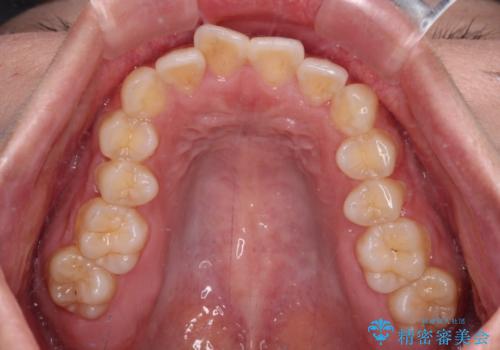

- 全体的なデコボコと口元の突出感を改善したいとのことで来院された患者様です。

このままデコボコを整えるとさらに突出感が増すため、上下左右の第一小臼歯を抜歯し、ワイヤー装置にて矯正しました。